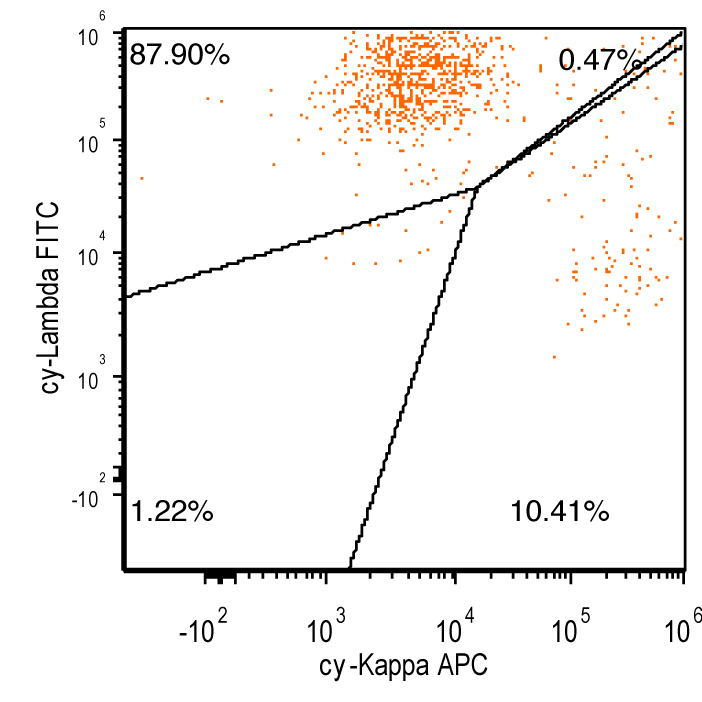

- Flow cytometry: monoclonal B cells with typical immunophenotype and monoclonal plasma cells

- Immunophenotype of LPL cells: IgM+, CD19+, CD20+, CD22+, CD25+, CD10-, CD23-, CD103-, variable CD138

- Immunophenotype

- Positive: IgM, CD19, CD20, CD22, CD79a, CD25 and CD38 frequent expression

- Negative: CD5, CD10, CD103, CD23; however, CD23 expression is not uncommon in some cases

Flow cytometry description

Flow cytometry images

Contributed by Ling Zhang, M.D. and Caroline An, M.D.